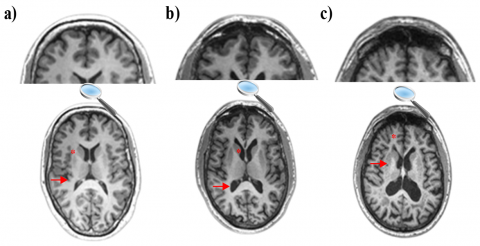

The increasing popularity of research on automatic classification of AD progression from MRI images using machine learning methods underlines the significant role of these methods in developing computer-based decision support systems [15]. Structural deformations in the brain of an AD patient, most often observed in the medial temporal lobes and hippocampus, can be perceived with the naked eye from an MRI scan [16, 17]. Figure 1 illustrates the MRI images of subjects with CN, MCI, and AD, showing the reduction in hippocampus tissue size and increase in ventricle size as the disease progresses.

Figure 5. Obtaining the dataset used in feeding the models

The images, after being downloaded to our local servers, were converted to 2D png images from 3D nifti files by using med2image software [42]. 3D TBM images are downloaded from ADNI. First, the height and width of each nifti file are saved. Witht this, axial images (z axis) were sliced at 5-pixel intervals starting from the 48th pixel to the 115th pixel, covering only the hippocampus and temporal lobe. As a result, 12 2D axial png brain slices were obtained for each subject. Considering that the hippocampus and temporal lobe are the regions most affected by AD, slices with these regions in the range of 48-115 pixels were taken [6]. The steps for converting TBM images from 3D medical image format to 2D png format are presented in Figure 5.

This study presents a new method to distinguish between AD, MCI, and CN stages using TBM and DL techniques. The study proposed three different models to differentiate between subjects. In addition, TBM-based analyses are compared with VBM-based analyses used in previous studies. Local morphological changes are helpful in identifying AD and MCI. As a result, TBM-based analyses achieve similar success levels compared to VBM-based analyses. The CNN-based methodology employed Within the confines of this study effectively discriminates between individuals with AD and those with MCI based on localized morphological alterations quantified through TBM. Consistent with its concept, TBM was useful only when the brain regions that are subject to the most severe local atrophy (namely, the hippocampi and temporal lobes) were used to feed the CNN algorithm. When medial slices from each axis were used, although they also contained meaningful information such as larger ventricles in AD subjects, the CNN algorithm was not able to capture the differences. However, this was not the case for the studies that used VBM or sMRI as input. A high level of predictive accuracy was reached for different 2D ROIs (covering the hippocampus). TBM is more suitable to diagnose diseases or abnormalities that are associated with a fairly small region in the brain, such as tumors, and the regions that are susceptible to atrophy should be chosen as the region of interest to run the prediction algorithm. The results show that TBM analysis using DL-based methods can be successfully used as an effective and usable method in the early diagnosis of Alzheimer's. Although the TBM contained information about minor regional differences, extracting more details using small kernels from the images did not significantly alter the model results. According to the results of all models in the study, DL-based systems can successfully perform early detection of Alzheimer's using TBM covering the hippocampus. In addition, TBM can be more successful than DBM-based morphometric methods in the early diagnosis of Alzheimer's.